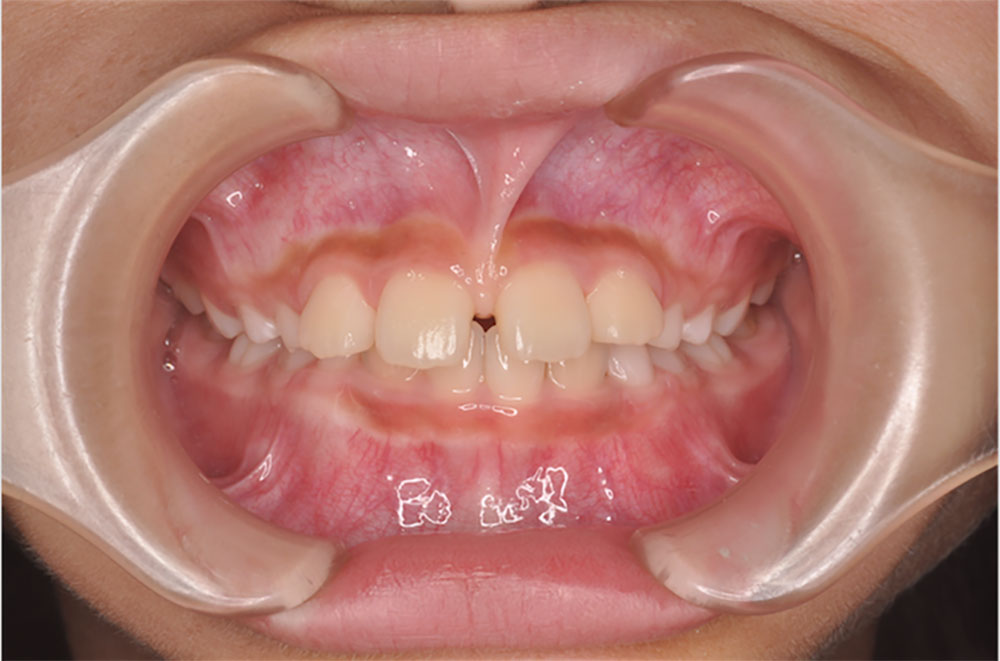

上唇小帯(じょうしんしょうたい)は、上くちびると歯ぐきをつないでいる「すじ」のことです。この小帯が上の前歯の真ん中付近に伸びてきていると、乳幼児健診等で指摘されることがあります。

小さなお子様のお口を診ていると、上の前歯と前歯の間に陥入するように小帯(すじ)が付着しているお子様が見受けられます。年齢が上がるとともに顎の成長発育につれて、正常になることもありますが、永久歯が出てくる頃に改善がみられないと、歯並びに大きく影響してしまいます。具体的には、一番前の前歯が左右離れてしまいます。このことを『正中離開』と言い、中心がすきっ歯になるので、歯並びだけでなく、顔貌にも悪影響が出てしまいます。

小学生1年生頃の前歯の生え代わりごろまでは様子を見ていて大丈夫ですが、すでに正中離開になっている、または前歯の永久歯が生え変わる頃に、小帯(すじ)が原因で、『正中離開』になりそうな場合は、小帯切除手術が必要となります。